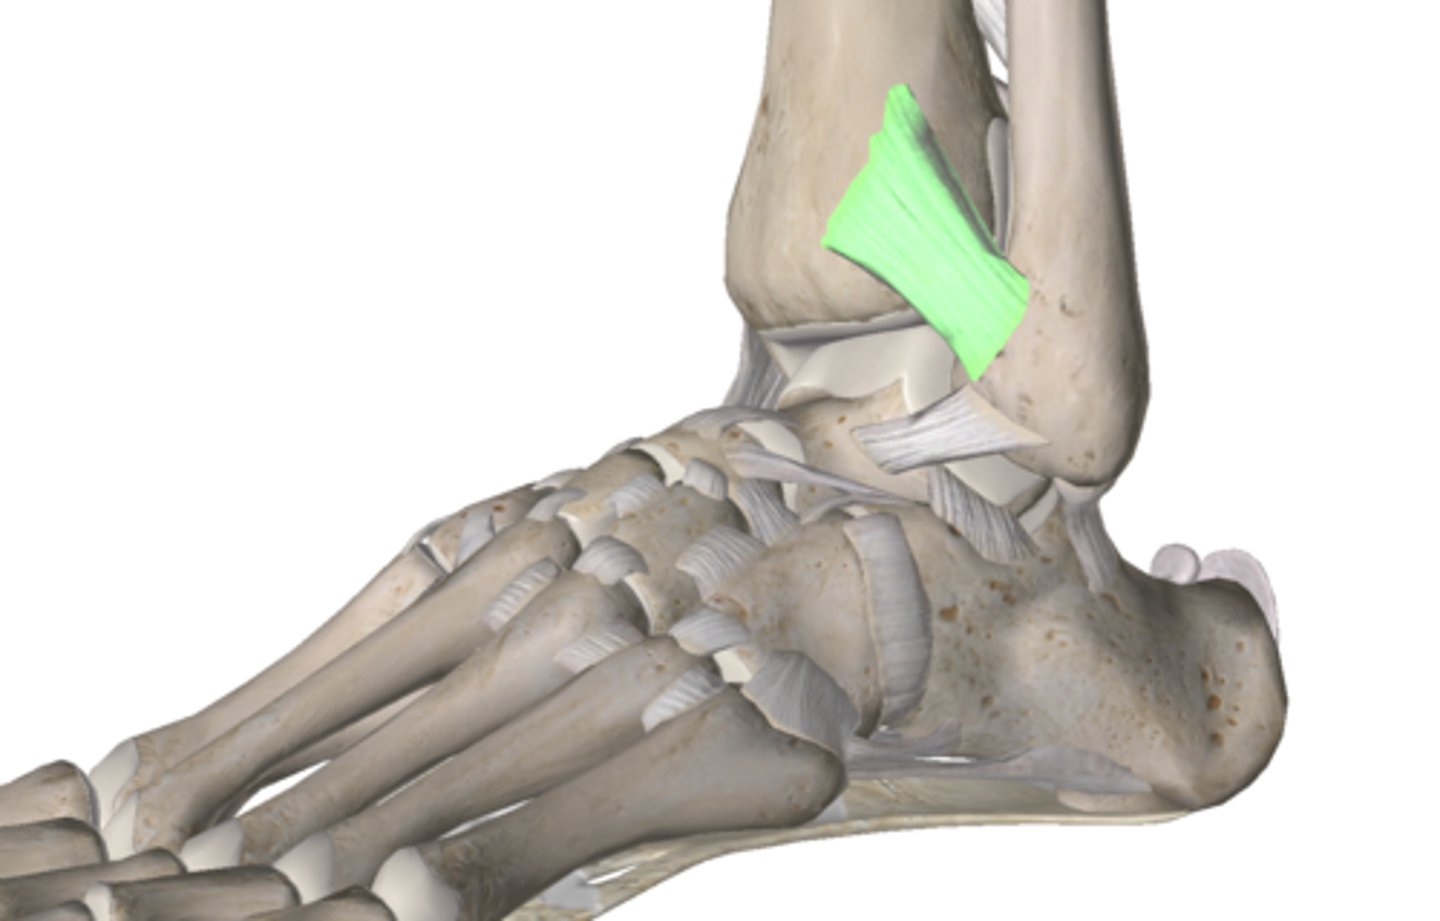

What ligament connects the distal end of the tibia to the fibula anteriorly?

anterior tibiofibular

What is the most common ankle sprain? What ligament is m/c affected?

inversion ankle sprain

- affects the anterior talofibular ligament

What test is used to assess the stability of the anterior talofibular ligament? What is a (+) test?

anterior drawer test

(+) → anterior dislocation; "clunk"

What are the THREE grades of ankle sprains?

Grade 1 → partial tear of the ATFL

Grade 2 → partial to complete tear of the ATLF + CFL

Grade 3 → complete rupture of the ATLF + CFL